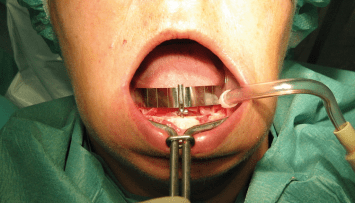

Die Endodontie hat in den vergangenen Jahren einen immensen Fortschritt erlebt. So können heute mit Zuhilfenahme moderner Geräte und Techniken auch Zähne erfolgreich erhalten werden, die noch vor geraumer Zeit als nicht erhaltungsfähig galten.